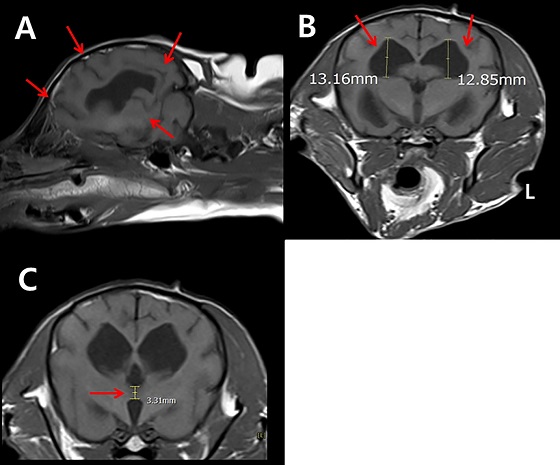

당시 1년 전부터 시작된 인지장애증상이 한 달 사이에 악화된 해당 반려견은 인지장애 설문평가에서 33점(10~41점 스케일)을 기록, 심각한 인지장애증상이 있는 것으로 확인됐다. 아울러 이안동물영상센터에서의 MRI 결과 뇌의 지주막하공간 및 뇌실의 확장, 시상간교 간격의 감소 등 뇌 실질 위축 소견이 발견됐다.

A. 시상단면에서의 지주막하 공간 확장

B. 단축단면에서의 뇌실 상대적 크기 증가

C. 단축단면에서의 시상단교 간격 감소

(자료 : 이안동물의학센터)